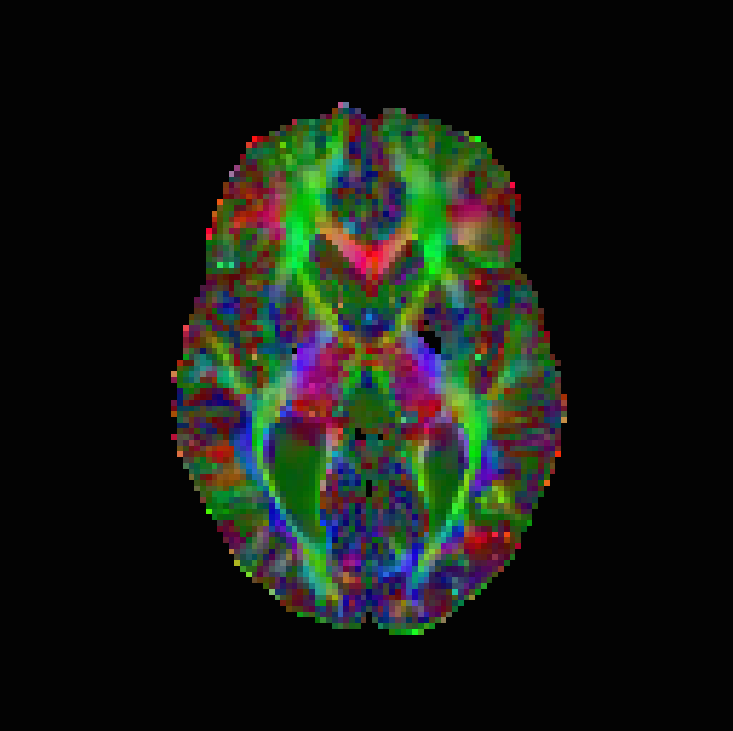

The numerical results are in Table 1 and Figures 3–5, with the first of the figures showing the colour-coded principal eigenvector of the reconstruction, the second showing the fractional anisotropy and principal eigenvectors, and the last one the errors in the latter two, in a colour-coded manner. All plots are masked to represent only the non-zero region. The field of fractional anisotropy is defined for a field of 2-tensors on as

As we can see, the non-linear approach (3.2) performs overall the best by a wide margin, in terms of the pointwise Frobenius error, i.e., error in . This is expressed as a PSNR in Table 1. What is, however, interesting, is that the constraint-based approach (3.5) has a much better reconstruction of the principal eigenvector angle, and a comparable reconstruction of its magnitude. Indeed, the 95% confidence interval in Figure 3(g) and Figure 4(g) suggests a nearly perfect reconstruction in terms of smoothness. But, the Frobenius PSNR in Table 1 for this approach is worse than the simple unregularised inversion by regression. The problem is revealed by Figure 5(f): the large white cloudy areas indicate huge fractional anisotropy errors, while at the same time, the principal eigenvector angle errors expressed in colour are much lower than for other approaches. Good reconstruction of the principal eigenvector is important for the process of tractography, i.e., the reconstruction of neural pathways in a brain. One explanation for our good results is that the regulariser completely governs the solution in areas where the error bounds are inactive due to generally low errors. This results in very smooth reconstructions, which is in the present case desirable as our synthetic tensor field is also smooth within the helix.

The results are in Table 2 and Figures 6–8, again with the first of the figures showing the colour-coded principal eigenvector of the reconstruction, the second showing the fractional anisotropy and principal eigenvectors, and the last one the errors in the latter two, in a colour-coded manner. Again, all plots are masked to represent only the non-zero region. In the figures, we concentrate on error bounds based on 95% confidence intervals, as the results for the 90% and 99% cases do not differ significantly according to Table 2.